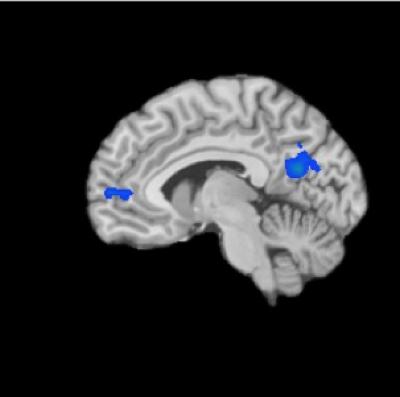

They found that experienced meditators had decreased activity in areas of the brain called the default mode network, which has been implicated in lapses of attention and disorders such as anxiety, attention deficit and hyperactivity disorder, and even the buildup of beta amyloid plaques in Alzheimer's disease. The decrease in activity in this network, consisting of the medial prefrontal and posterior cingulate cortex, was seen in experienced meditators regardless of the type of meditation they were doing.

The scans also showed that when the default mode network was active, brain regions associated with self-monitoring and cognitive control were co-activated in experienced meditators but not novices. This may indicate that meditators are constantly monitoring and suppressing the emergence of "me" thoughts, or mind-wandering. In pathological forms, these states are associated with diseases such as autism and schizophrenia.